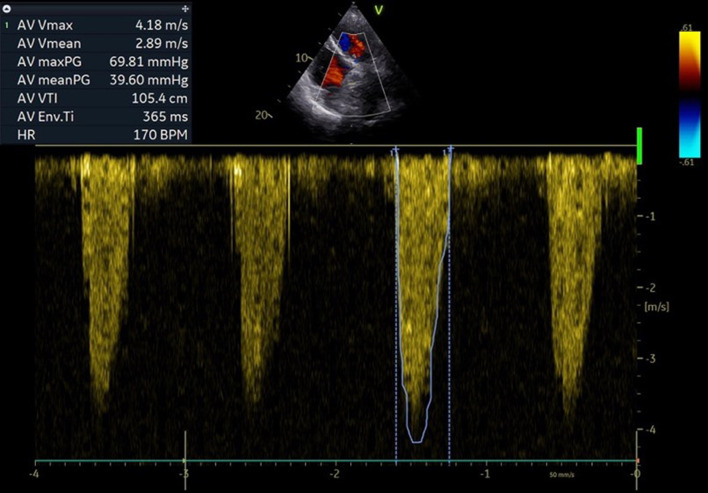

The natural progression of bioprosthetic valve degeneration over time requires further interventions for those experiencing symptomatic prosthesis dysfunction. Transcatheter aortic valve replacement (TAVR) emerges as a promising therapeutic option to alleviate symptoms in such patients. The valve-in-valve (ViV) technique eliminates the necessity for repetitive open-heart surgical procedures, offering particular advantages for individuals with higher surgical risks. In this report, we describe the case of a 78-year-old female patient presenting with severe symptomatic aortic restenosis of a biological aortic valve implanted 5 years prior. Given the patient's high surgical risk, a transcatheter ViV implantation was chosen as the treatment approach. Utilizing a balloon-expandable valve, the intervention resulted in the successful implantation of a functional TAVR, resulting in symptom relief and enabling a fast discharge from the hospital.